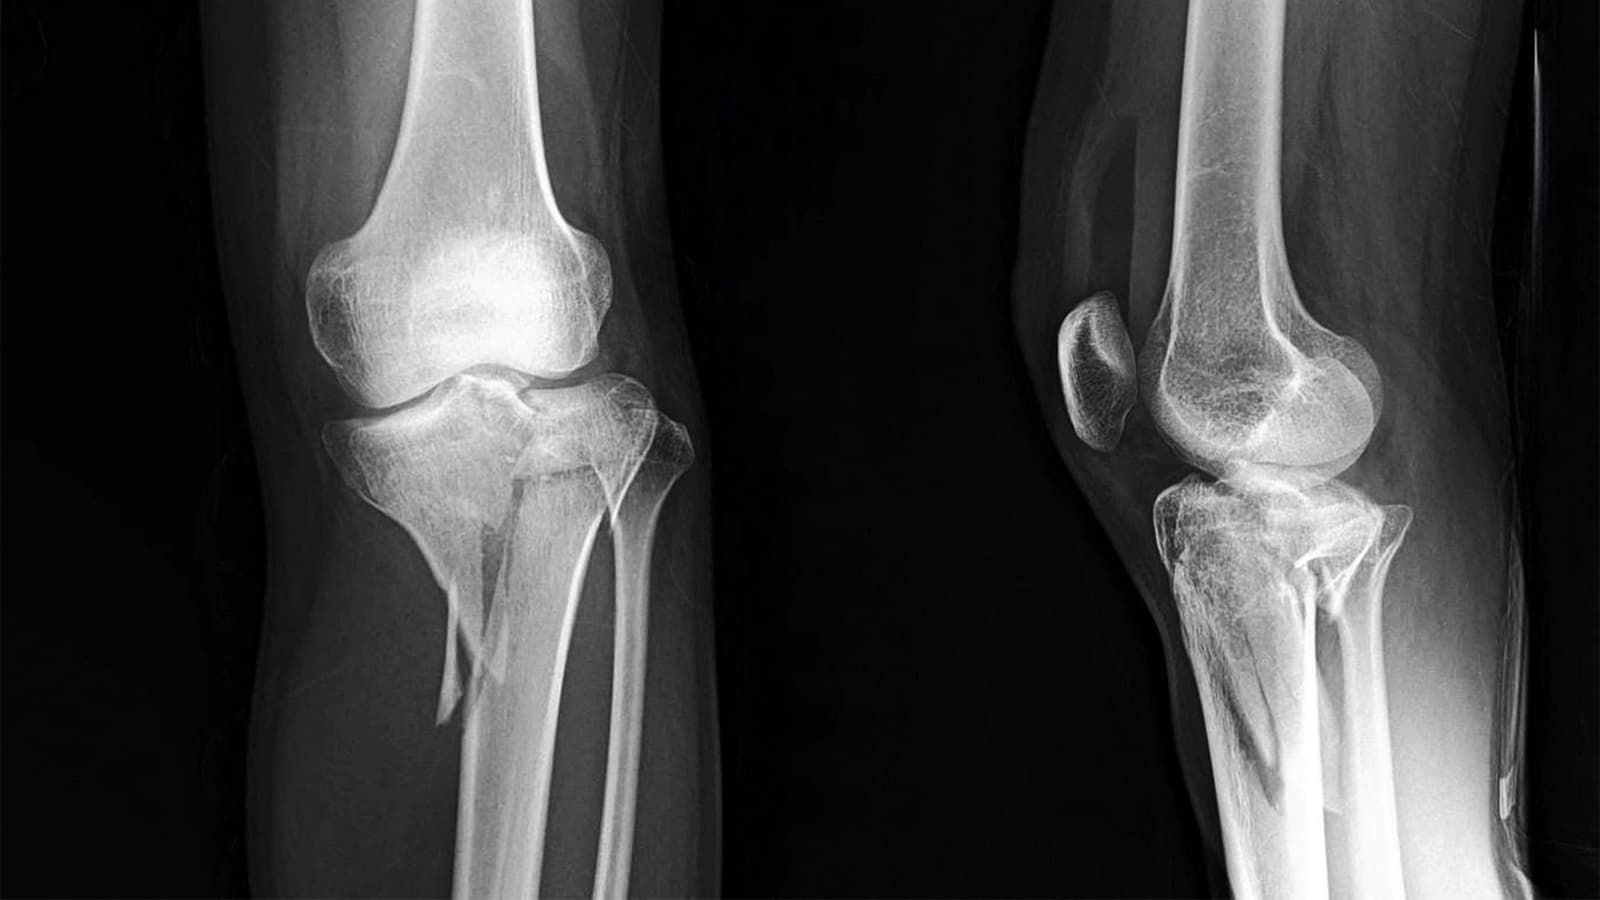

One Intrawound Antibiotic Wins for Surgical Infections After Tibial Fracture Surgery

(MedPage Today) -- Pairing intrawound tobramycin with vancomycin powder was no better than vancomycin alone at preventing deep surgical site infections among patients with periarticular tibial fractures at high risk of infection, the randomized...